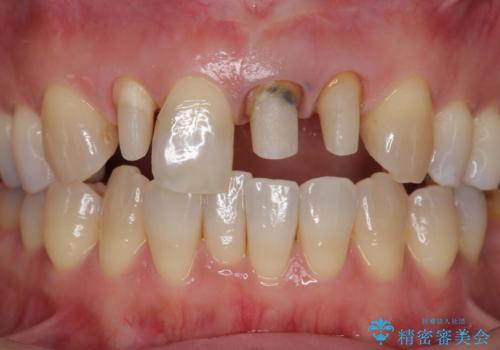

- 前歯のクラウンの歯肉の位置が年々変化し、歯ぐきのフチが黒くなってしまった、綺麗にしたいと希望されて来院されました。

装着されているセラミッククラウンを除去したのち、現在の歯ぐきのラインにしっかりと合う精度の高いオールセラミッククラウンを作製していきます。